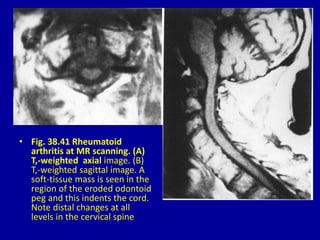

• Fig. 38.41 Rheumatoid

arthritis at MR scanning. (A)

T,-weighted axial image. (B)

T,-weighted sagittal image. A

soft-tissue mass is seen in the

region of the eroded odontoid

peg and this indents the cord.

Note distal changes at all

levels in the cervical spine

• Fig. 38.41Rheumatoid arthritis at MR scanning. (A) T,-weighted axial image. (B) T,-weighted sagittal image. A soft-tissue mass is seen in the region of the eroded odontoid peg and this indents the cord. Note distal changes at all levels in the cervical spine